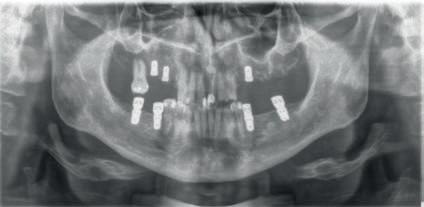

Figura 5. Imagen radiográfica mostrando el resultado del primer acto quirúrgico de la extracción de ricas dentales remanentes y la inserción de implantes dentales. Los implantes en el maxilar inferior recibieron carga inmediata sobre componentes transepiteliales Multi-Im®.

En el primer acto quirúrgico fueron extraídas todas las raíces dentales remanentes y regeneradas con el uso de plasma rico en factores de crecimiento (Endort (PRGF). También se insertaron dos implantes (UnicCa®, BTI Biotechnology Institute, Vitoria) de 4,5 mm X 7,5 mm y 5,0 mm X 7,5 mm en las posiciones del primer y segundo molar del cuarto cuadrante, respectivamente. Mientras en el tercer cuadrante se insertaron dos implantes de 4,5 mm X 7,5 mm y 5,0 mm X 6,5 mm en las posiciones del primer y segundo molar, respectivamente. En el mismo acto quirúrgico se insertaron dos implantes de 4,0 mm X 7,5 mm y 4,5 mm X 7,5 mm en las posiciones del primer y segundo molar del primer cuadrante. Otro implante de 4,5 X 7,5 mm fue insertado en la posición del primer molar en el segundo cuadrante. La presencia de buena calidad ósea (tipo III) y la consecución de un torque de inserción mayor de 30 cm hizo posible la carga inmediata de los implantes en el maxilar inferior. Por ello, se insertaron componentes transepiteliales Multi-Im® (BTI Biotechnology Institute, Vitoria). La toma de medidas se hizo con la técnica de cubeta abierta y el uso de análogos

de impresión de Multi-Im®. La prótesis provisional metal-resina fue colocado durante las primeras 24 horas después de la inserción de los implantes dentales. Sin embargo, en el maxilar superior se decidió la realización de una carga tardía debido a la presencia de hueso alveolar de baja calidad.